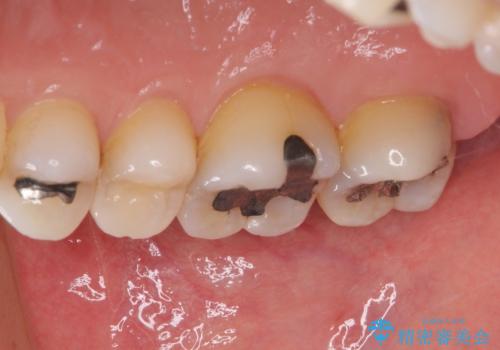

- 奥歯に装着されてい銀歯の中が虫歯になってしまったとのことで来院された患者様です。

虫歯をしっかりと取り除き、ゴールドインレー(PGAインレー)にて修復することとしました。